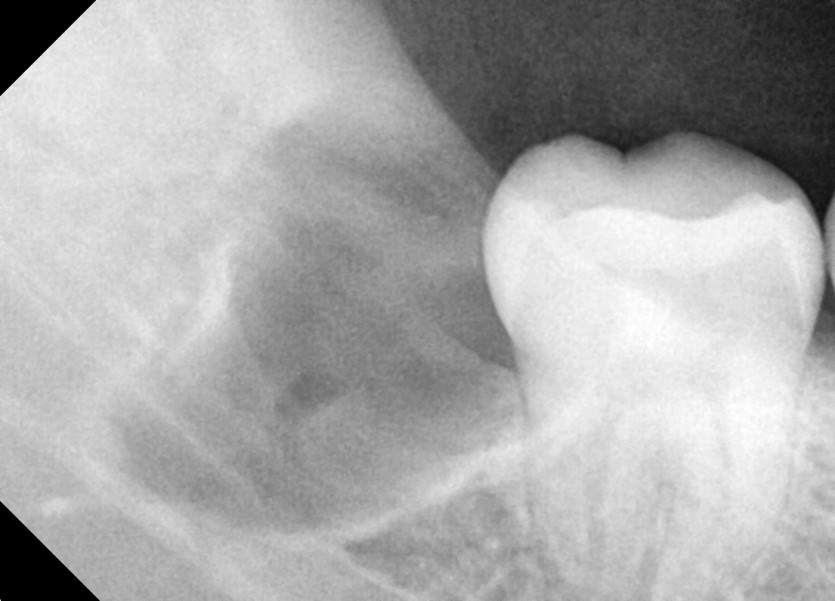

#38,48 사랑니 발치

구강 외과 전문의가 당일 발치했습니다.